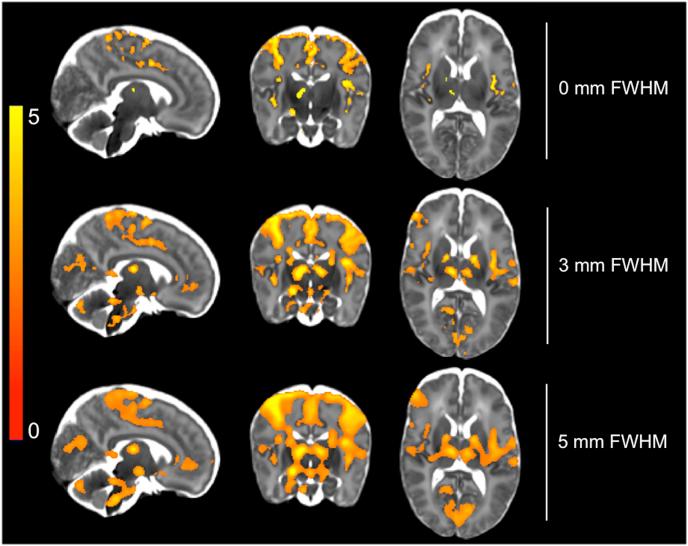

The infant brain is unlike the adult brain, with considerable differences in morphological, neurodynamic, and haemodynamic features. As the majority of current MRI analysis tools were designed for use in adults, a primary objective of the Developing Human Connectome Project (dHCP) is to develop optimised methodological pipelines for the analysis of neonatal structural, resting state, and diffusion MRI data. Here, in an independent neonatal dataset we have extended and optimised the dHCP fMRI preprocessing pipeline for the analysis of stimulus-response fMRI data. We describe and validate this extended dHCP fMRI preprocessing pipeline to analyse changes in brain activity evoked following an acute noxious stimulus applied to the infant's foot. We compare the results obtained from this extended dHCP pipeline to results obtained from a typical FSL FEAT-based analysis pipeline, evaluating the pipelines' outputs using a wide range of tests. We demonstrate that a substantial increase in spatial specificity and sensitivity to signal can be attained with a bespoke neonatal preprocessing pipeline through optimised motion and distortion correction, ICA-based denoising, and haemodynamic modelling. The improved sensitivity and specificity, made possible with this extended dHCP pipeline, will be paramount in making further progress in our understanding of the development of sensory processing in the infant brain.